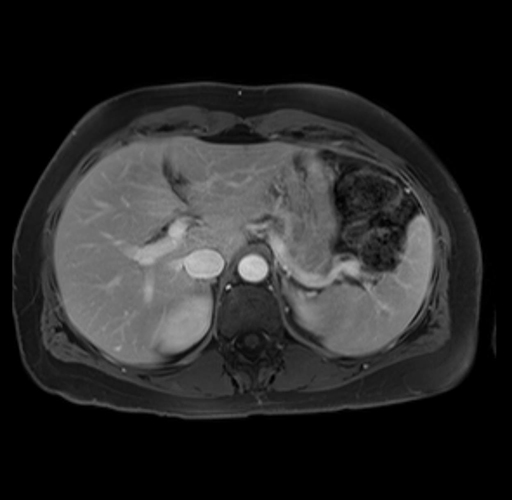

Imaging Analysis

Look through the patient's CT scan to identify any areas of concern for the necessary procedure.

Based on your CT findings, which issue(s) are present and would give reason for "planned slowing down moment(s)" in this case?